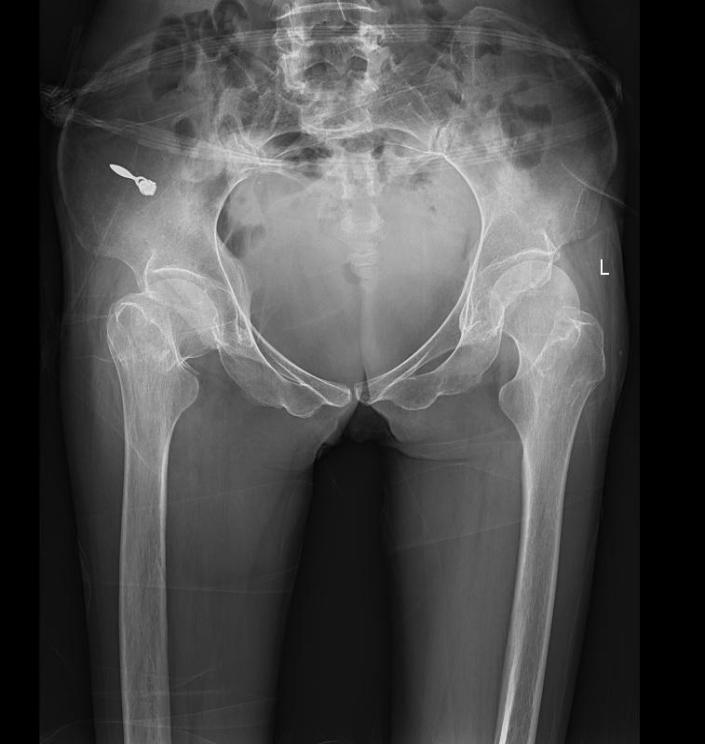

据悉,该患者为女性,现年53岁,形体瘦弱,体重仅25kg,心肺功能较差,因跌倒导致右侧股骨颈骨折,于4月30日被家属送入新平县中医医院进行治疗。骨伤科医疗团队经影像检查发现,患者患有先天性脊柱侧弯、脊柱后凸畸形,胸廓畸形、双上肢屈曲挛缩畸形和先天性马蹄内翻足畸形,四肢发育不良、关节强直。如不及时予以治疗,后期极可能因骨折端不愈合,导致患者长期卧床,使患者右下肢负重功能和行走功能完全丧失,并面临长期卧床带来的各种并发症,甚至危及生命。为了消除患者的痛苦,让患者早日恢复健康,骨伤科医疗团队综合研究患者病情,于5月6日对患者实施高精miniKL微创技术行全髋关节置换术。术中出血量较少,手术时间短,极大地减少了术后感染等并发症。本次手术切口仅7厘米,术后患者即可自由抬腿,右髋关节稳定性良好。鉴于骨科康复能有效加快患者的康复进程,骨伤科医疗团队与针灸科医疗团队密切配合,为患者制定了科学、安全、个体化的康复方案。经过骨伤科医疗团队与针灸科医疗团队的不懈努力,以及患者持之以恒的刻苦训练,目前,患者已能顺利下地行走,患者和家属对治疗效果非常满意。   近年来,新平县中医医院骨伤科医疗团队不断挑战高难度手术,以精湛的医疗技术为骨关节疾病患者的健康保驾护航,让广大骨关节疾病患者在县域内就可以享受到高精尖医疗技术带来的健康生命质量。